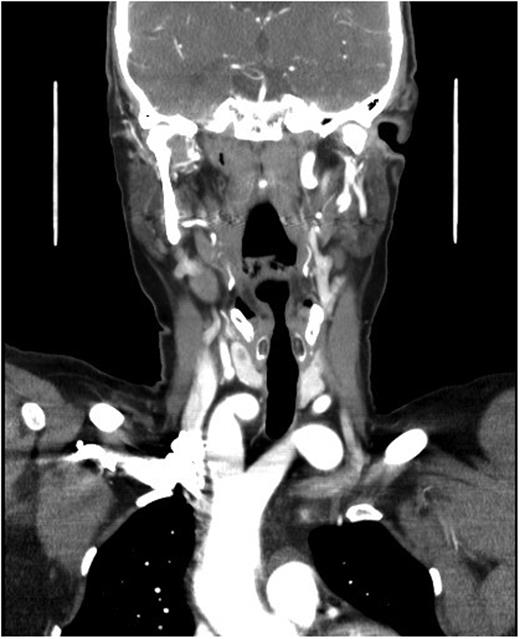

A duplex scan performed on this presentation demonstrated a high, prominent and ectatic aortic arch visible above the sternum, with a diameter of 2.0 cm. The innominate artery appeared ectatic, tortuous with localized wall thickening and had a reported diameter of 1.8 cm. An outpatient computed tomography (CT) angiogram was arranged to help delineate the underlying anatomy. Figure 3 shows a coronal section of this CT angiogram. Figures 4 and 5 show the anterior and posterior views of the 3D reconstruction, respectively.

Figures 3–5 demonstrate a DAA with the right carotid and right subclavian arteries arising from the right-sided arch and left carotid and left subclavian arteries from the left-sided arch. There is also a minor narrowing of the right-sided arch at a kink between the right carotid and subclavian origins. Figure 3 demonstrates both arches rising up into the neck explaining the clinical presentation.